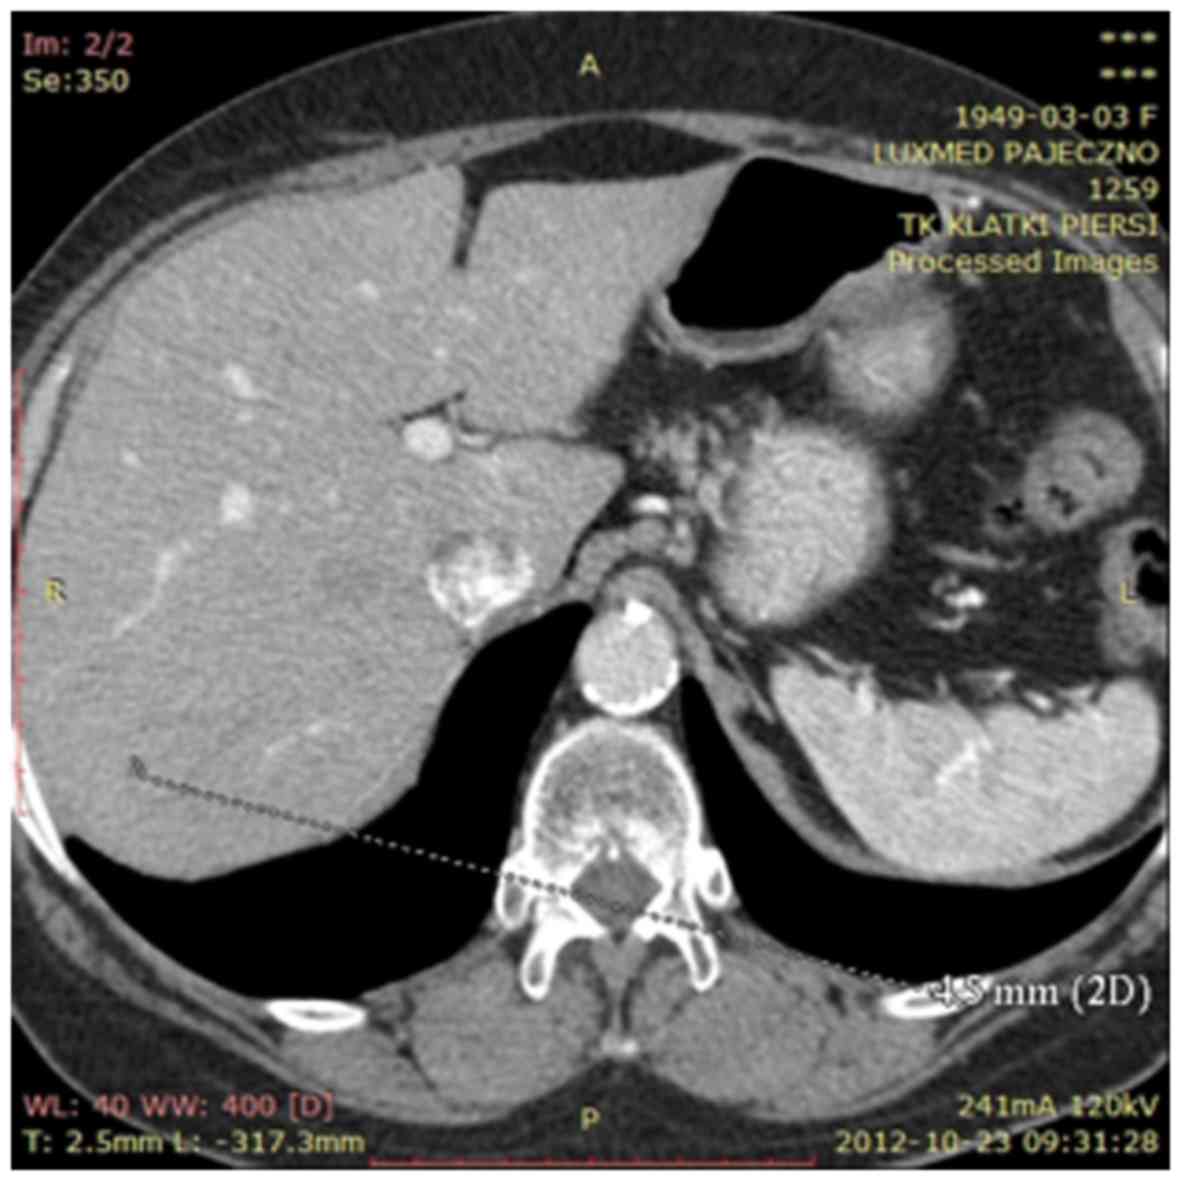

Figure 2.

Computed tomography metastasis to the liver at the time of diagnosis.